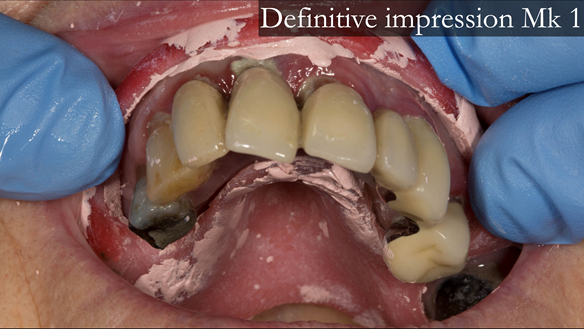

This newsletter describes in step by step detail Anne's transition from an immediate complete upper denture to a definitive complete upper denture.

The clinical situation and treatment process is shown in detail below with photographs. In addition, threre is a link to the a 45 minute webinar I gave explaing this case. I provided the clinical work and Rowan Garstang provided the technical work.